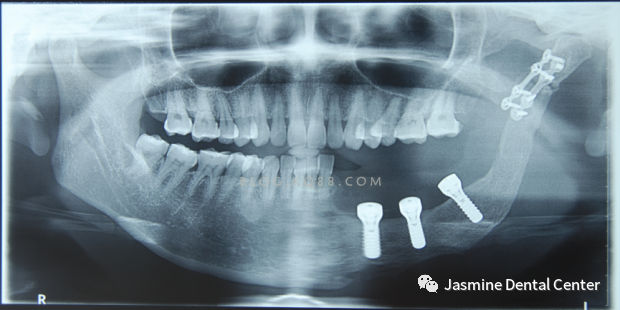

6、垂直方向的骨吸收不超过种植手术完成时植入在骨内部分长度的1/3(采用标准投照方法X光片显示)。横行骨吸收不超过1/3,种植体不松动。

7、放射学检查,种植体周围骨界面无透影区。